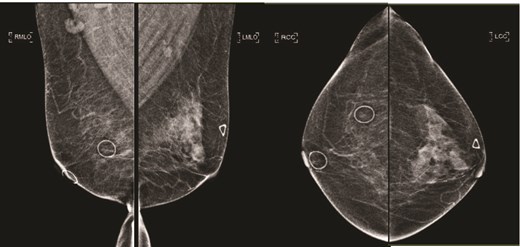

(Left) Ultrasound images of the left breast ill-defined hypoechoic mass; (Middle, Right) Ultrasound images of the axillary lymph nodes with cortical thickening and effacement of the fatty hilum.

(Left) Mammography medioloateral oblique views of bilateral breasts; (Right) Mammography cranial-caudal views of bilateral breasts: Left upper central breast shows a vague focal asymmetry corresponding to the palpable concern, and several prominent right axillary lymph nodes.